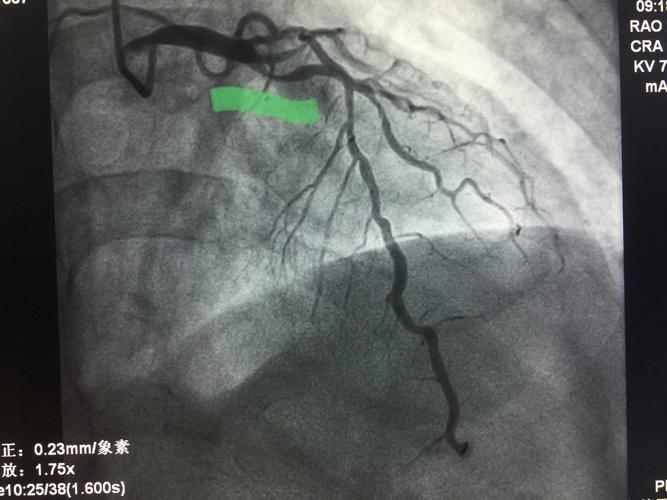

造影提示三支弥漫性病变,acc/aha冠脉病变分型:c型,synta